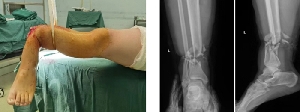

足踝外科成功完成1例小腿離斷再植術(shù)

近日,在手術(shù)室護(hù)理團(tuán)隊(duì)、麻醉科團(tuán)隊(duì)等科室的積極協(xié)助下,我院足踝外科歷時(shí)7個(gè)多小時(shí)成功完成1例“小腿離斷再植術(shù)”。當(dāng)晚,值班醫(yī)師接到會(huì)診電話:患者趙某,男,29歲,因鋼板砸傷致左小腿離斷2小時(shí)急診入院。經(jīng)初步評(píng)估,患者傷口遠(yuǎn)端組織離斷,僅少許皮膚相連,遠(yuǎn)端肢體無血運(yùn),創(chuàng)口內(nèi)組織毀損嚴(yán)重。經(jīng)與患者及其家屬充分